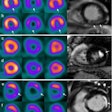

Winter is a SPECT time of year: Imaging frostbite